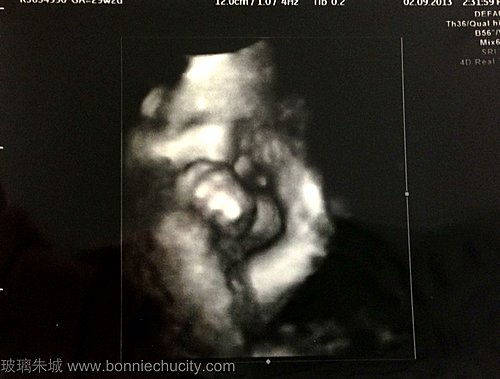

終見BB真面目

昨天再去覆診,BB十分健康。而且今次終於可以看到他的整張臉了!每次照4D,他都會用手遮著臉,真是十分神秘。今次開始時也是這樣,到過了一會,看見他打呵欠,才見到他的真面目... BB有個很高很大的鼻子,哈哈大鼻像我高鼻像老外榮。輪廓很分明,應該也是"靚仔"一名啦。其實之前幫KEON擇日時,已經大約知道他是一個怎樣的人。知他應該桃花很重,有點脾氣及反叛受軟不受硬,要講道理<---這個似媽咪。其實最重要是他可以身體健康,亦要做一個好人便夠了。... 看全文 -